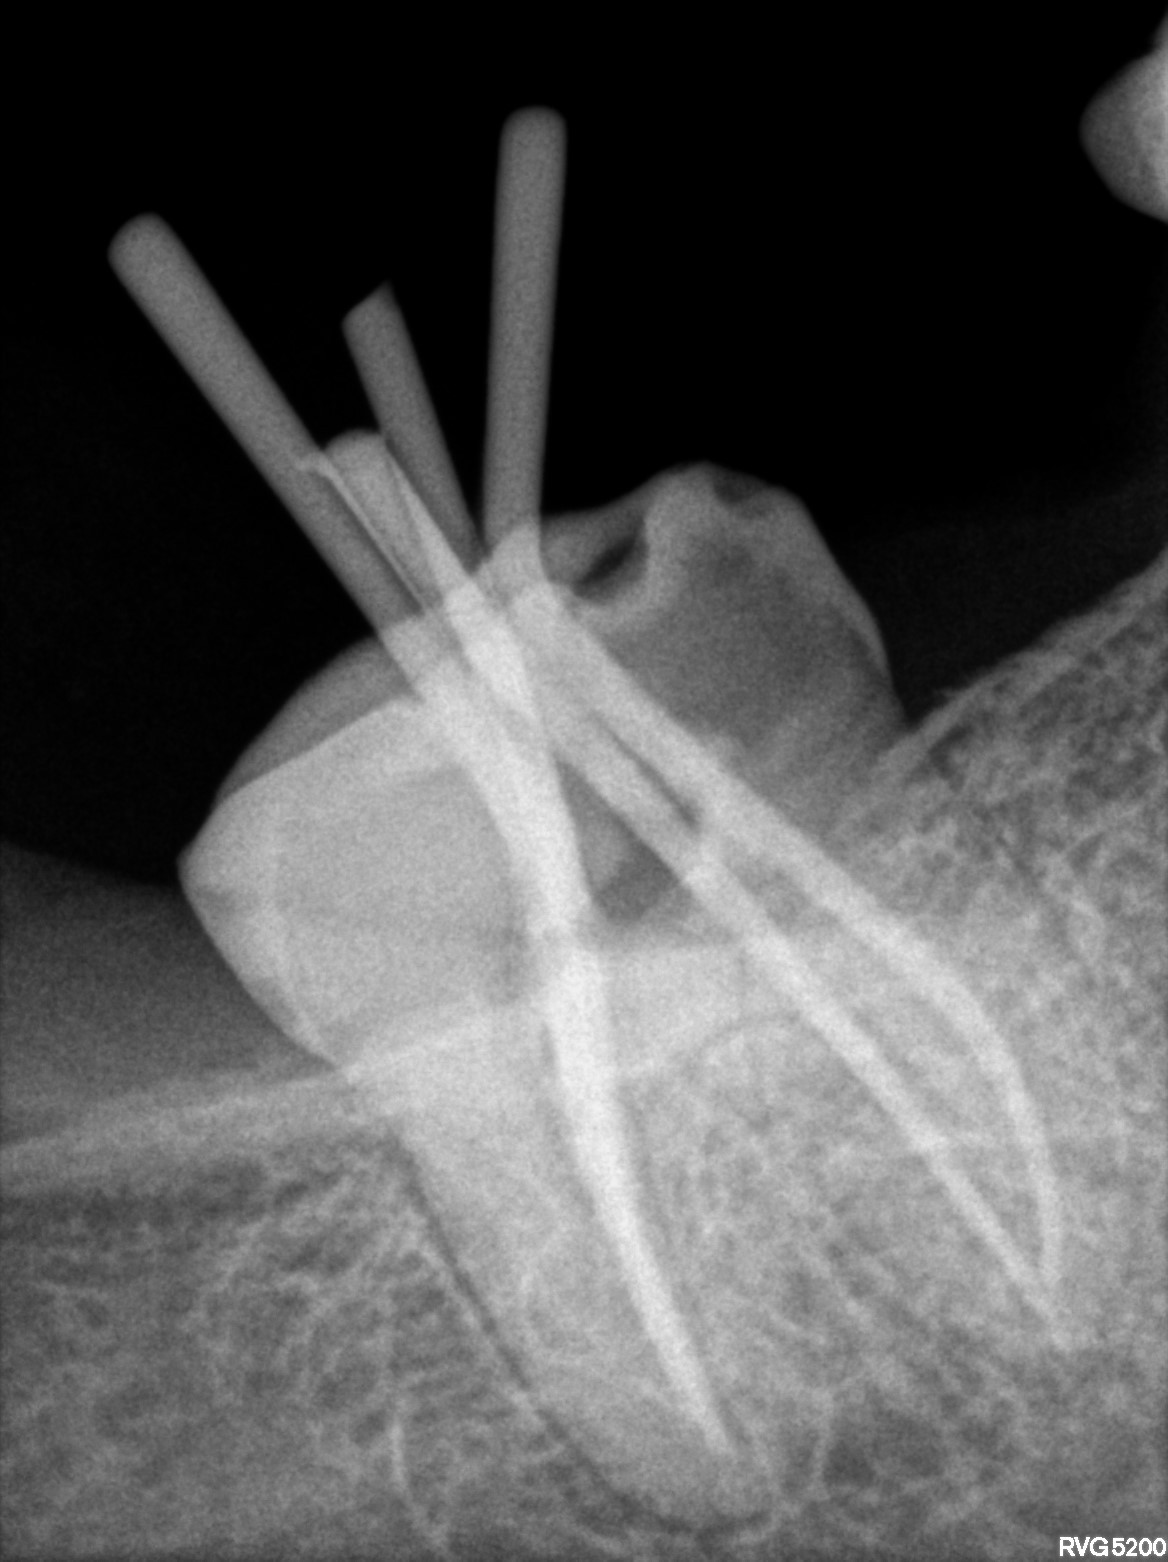

Dental Radiographs FHIR: DocumentReference · LOINC 24641-7

xray_1758897542_1.jpg

24641-7

| Root canal treatment | 234780006 | D3330 Endodontic therapy, molar tooth | ##47, #45 | 2025-09-26 | completed | obt 47,45 | |

| Root canal treatment | 234780006 | D3330 Endodontic therapy, molar tooth | ##25 | 2025-09-22 | completed | bmp 25.04 increased 2 stopper all 4 canals | |

| Root canal treatment | 234780006 | D3320 Endodontic therapy, premolar tooth | ##45 | 2025-09-19 | completed | a/o with 45, bmp 25.06 till apex | |

| Root canal treatment | 234780006 | D3330 Endodontic therapy, molar tooth | ##47 | 2025-09-19 | completed | a/o 47, bmp 25.04 till apex all 4 canals | |